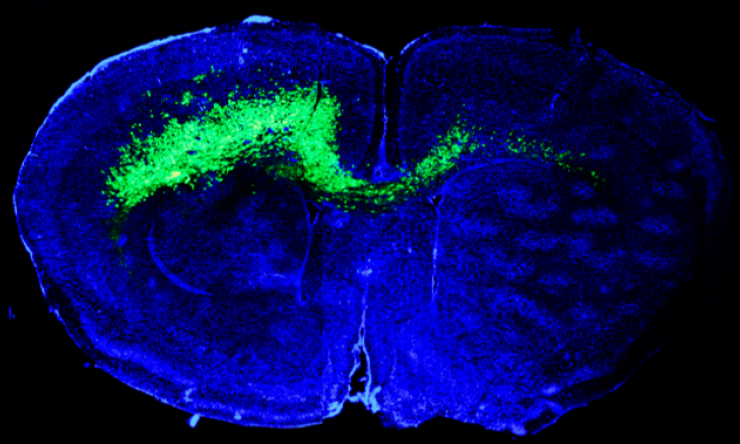

In the study, which is published in the journal Nature Neuroscience, the scientists report that the emergence of specific brain cells during brain tumor progression in a mouse model marked the onset of seizures and brain tumor invasion. An improved understanding of how brain tumors cause seizures can potentially lead to strategies to prevent them or treat them.

To support that astrocytes seemed to play a role in human glioblastoma, the researchers genetically engineered two mouse models of the disease and observed that the astrocyte subpopulations are also present in mouse tumors. The subpopulations are also present in primary human specimens of human glioblastoma multiforme.

The results of these experiments showed that as the tumor grows, the excitability of the adjacent neurons progressively increases. Seventy days after birth, the mice had visible seizures that correlated with the emergence of astrocyte subpopulation C. Further linking these astrocyte-like subpopulations to seizures, the scientists showed that subpopulation C expresses a significant number of genes linked to epilepsy.